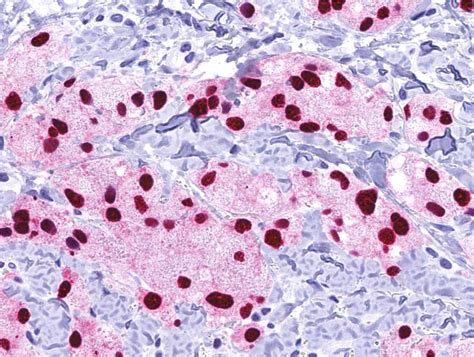

The histopathological features of granular cell tumours are distinctive and play a crucial role in their diagnosis. Key features include:

• Large, polygonal cells with abundant granular cytoplasm

• Small, centrally located nuclei

• Abundant lysosomes within the cytoplasm

• Positive staining for S-100 protein, a marker for neural and melanocytic differentiation

These features help differentiate GCTs from other types of tumours, such as rhabdomyomas and alveolar soft part sarcomas, which may have a similar appearance but different clinical behaviours.